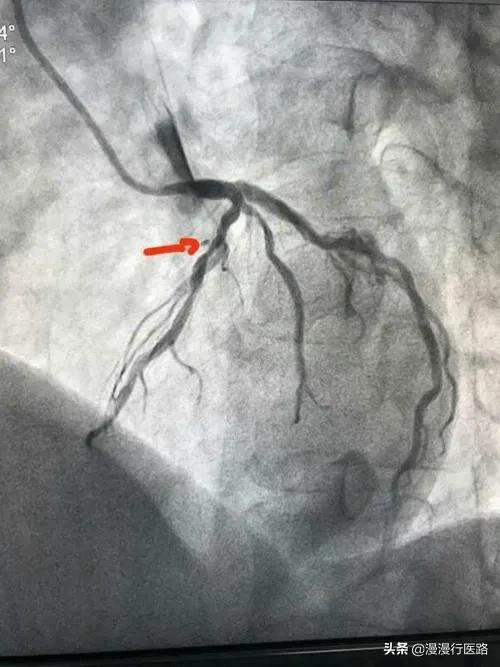

再三の説得の結果、ラオフーは入院することになり、私はラオフーに心電図検査を受けるよう手配した。その結果、左側の血管が99%狭くなっており、適時発見したおかげですぐにふさがることがわかった。しかし、国内のステントは7,500円、その他の手術器具も数万円する。老福のような家族にとって、これは実に重荷であった。 たまたま、王医師がステント留置のプロセスに関する臨床研究という実験の責任者であったので、彼は老福に、この研究に参加する意思があるかどうか、無料でステントを留置することができるかどうかを告げた。ラオフーは快く承諾した。何しろ1万元近く節約できるのだから。ラオフーを病室に送り返すとき、ラオフーはまだ心配そうに、どうしたのかと彼に尋ねた。

その後、関連する検査を手配し、画像診断の結果、左冠動脈の狭窄が85%に達しており、ステント留置が必要であることがわかった。

張さん、あなたの左冠動脈の狭窄の程度は85%に達しており、最後の比較は明らかに深刻です。